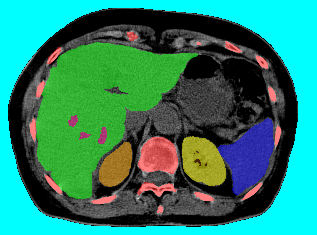

Abdominal Organ Segmentation:

We used CT dataset and extended the work in [13] which used Hedgehogs to segment liver and kidneys. In contrast to [13], we utilized more detailed structures reaching labels.

For each test case we computed the weighted precision

where is the ground truth labeling. The weighted recall is defined similarly. As shown in Table 3, all methods performed comparably due to the use of Hedgehog priors and the star-like structure of , which -exp is well suited for. See Table 4 for results without using Hedgehog priors. Figure 18 shows the tree and our result for one test case. Interestingly, QPBO labeled all the pixels in all 7 test cases. By comparing Tables 3 and 4 it is easy to see the benefit of using Hedgehog priors. Moreover, Path-Moves outperformed QPBO and a-exp after dropping the Hedgehog priors.

|

| (a) tree | |